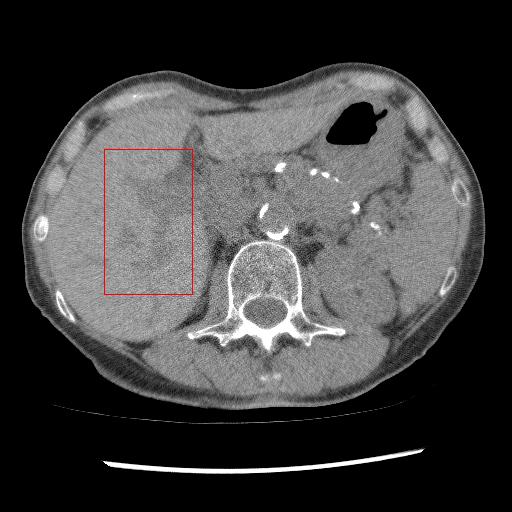

Figure 5: Performance of invertible network in reverse mapping. The display window for CT images is [160160-160, 240] HU, and for noise pattern [5050-50, 50] HU

This section systemically investigates the efficacy of every module proposed in this study. We considered three different networks; first, baseline model(M1), where the inverting block is replaced with dense block, and trained using minimizing mean square distance between two noisy observations(i.e. fsubscript𝑓\mathcal{L}_{f}). Next, two independent baseline model(one for forward mapping, one for reverse mapping) is jointly trained using a linear combination fsubscript𝑓\mathcal{L}_{f}, and rsubscript𝑟\mathcal{L}_{r}, similar to cycle consistent network paradigm. The forward mapping network is used for testing. We refer this model as M2. In both M1, and M2, we increased the depth of the network to make the representation power of these networks comparable with inverting network. Finally, the proposed method, referred as M3. Table 2 depicts the objective evaluation of the three networks using the D1 dataset. Both M2 and M3 use reverse mapping to regularize the network; the influence of the same in the denoising performance is evident from Table 2. Adding cycle consistency loss has improved the performance of the same baseline model significantly. The inverting network performed considerably better than the network M2. It improves PSNR by 0.23dB. As discussed in the above section, in case cycle consistency loss, an additional network is trained, but that does not always guarantee invertibility, whereas inverting network architecture inherently possesses reversibility, which acts as a strong regularizer. In Figure 3 we have shown denoising performance of different networks visually. To demonstrate the requirement of regularization, we first extract the boundary line of the various organ from the NDCT image and superimpose the boundary line on the output of different networks. As shown in Figure 3, many pixels around the boundary line of M1 network output are missing. Using the reverse mapping, the issue of the end-organ missing pixel is successfully overcome in M2 and M3. The granular pattern is also less present in the M3 than M2. The zoomed version of a ROI taken from the images of Figure 3 is given in Figure 4 for better perception. In Figure 5 we give an example of the performance of the invertible network in reverse mapping. Here, the predicted LDCT image is produced by using the predicted clean image of the forward mapping as the input for reverse mapping. As shown, the predicted noisy pattern is similar to the original noise pattern. The same streaking artifacts are present in both the noise pattern; also, the noise variance is different in the various spatial region depending on the signal intensity of the original CT image. It validates that the loss of information in reverse mapping is minimal. Due to the invertible network’s structural advantage, the network also preserves every information present in the input image in the forward mapping.